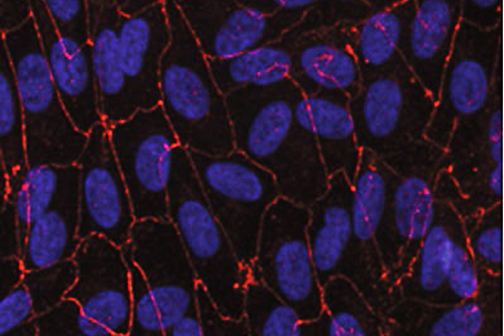

LSU Health New Orleans Develops New Human Cell Line to Study Blinding Eye Disorders

Under the direction of Boyd Professor Nicolas Bazan, MD, PhD, scientists at LSU Health New Orleans Neuroscience Center of Excellence have developed a new, experimental human cell line from retinal pigment epithelial cells. Called ABC, these cells so closely resemble and retain the properties of native retinal pigment epithelial (RPE) cells, the research team has shown that they are a reliable cell system to study retinal degenerative diseases. More